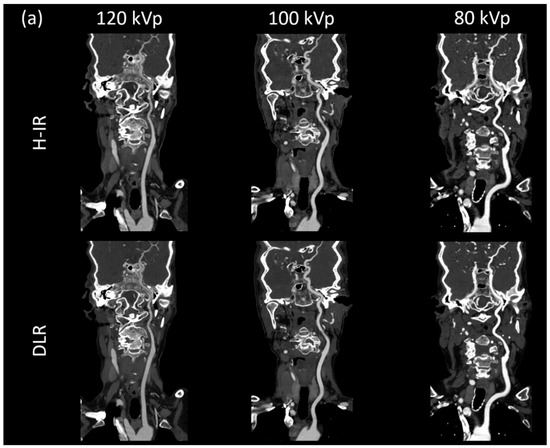

3.3.1. Image Signal Fluctuation with DLR vs. H-IR

3.3.2. Comparison of the Two Reconstruction Techniques at Constant kVp Value